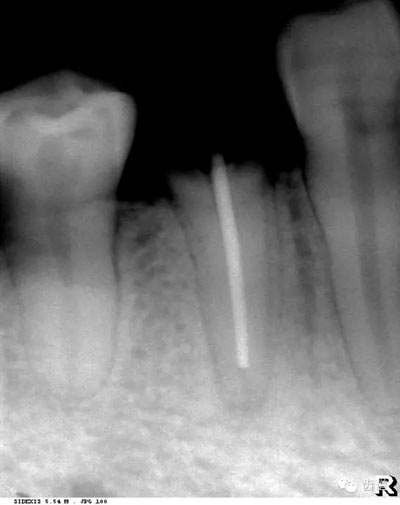

5)下頜管:

位于磨牙牙根尖下方,呈寬約為0.4cm凹面向下邊緣整齊的帶狀密度低的影像,其兩側(cè)有密度高的線條狀影像,為下頜管骨密質(zhì)